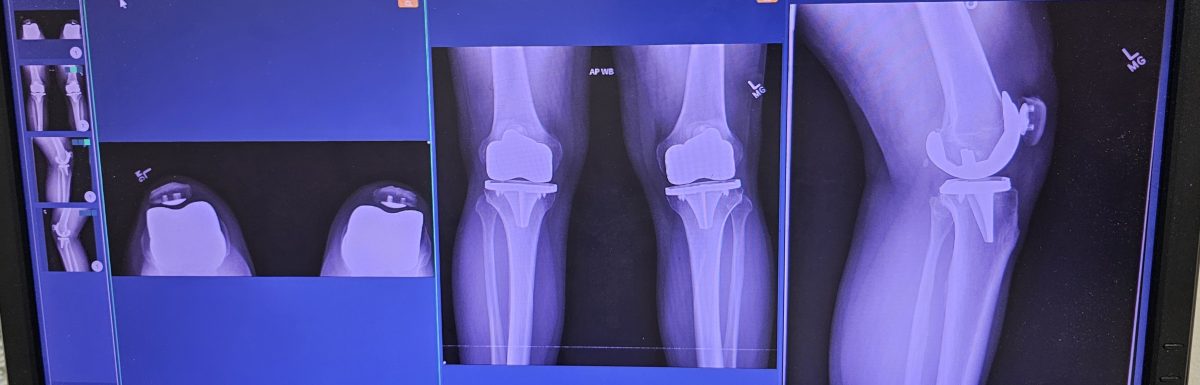

There comes a moment in every serious martial artist’s life when the body begins to speak more loudly than the ego. For some, it’s a minor injury. For others, like myself, it is something far more profound— two shoulder surgeries, bilateral knee replacements, foot surgery, the kind of life events that forces a complete reevaluation of what it means to train, to progress, and ultimately, to walk the martial path.

After my surgeries, I could no longer train the way I once did. Deep stances, ballistic movements, and repetitive impact required careful reconsideration. At first, this felt like regression. In truth, it was refinement.